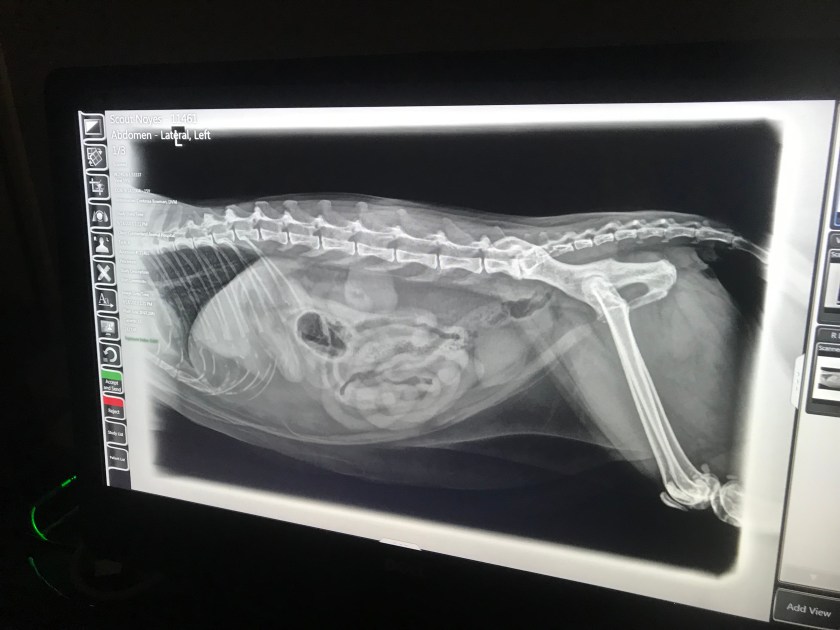

This afternoon I took my Scout for a follow up visit. She’d lost a half a pound, and for a 10 pound cat that’s significant. I told the vet that Scout’s still puking a bit after every meal even without treats. She took some x-rays, and the great news is there’s no tumor.

However, one of her kidneys is smaller than the other, and her liver has shrunk. Neither of these would result in her puking, though.